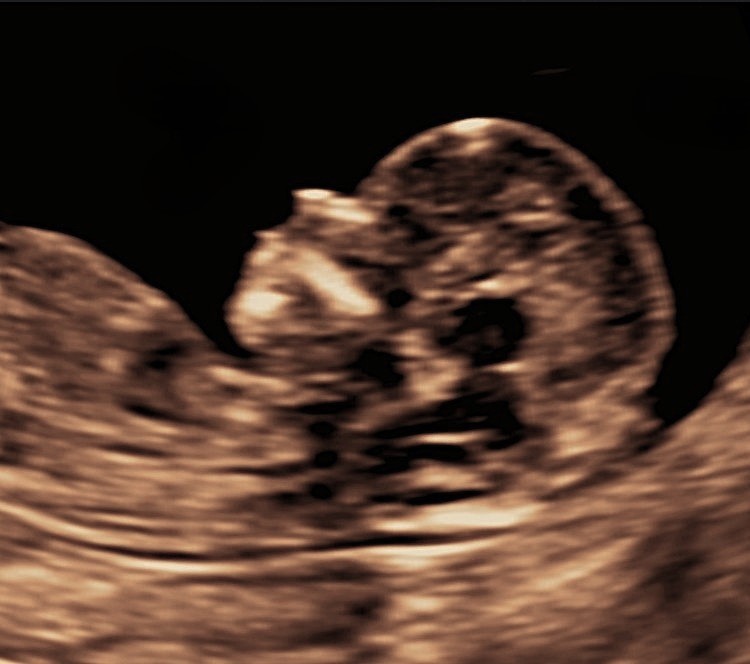

A comprehensive first trimester assessment – More than just pregnancy dating and screening for genetic conditions

The nuchal scan is one of the most important early appointments in pregnancy and is performed between 11 and 13 weeks. It provides a comprehensive assessment of the health and wellbeing of the pregnancy, including a personalised evaluation of the risk of common pregnancy-related conditions.

At The Pregnancy Clinic, the nuchal scan goes beyond confirming dates and screening for genetic conditions. We carry out a detailed early assessment of your baby’s development and offer evidence-based screening for pregnancy complications such as pre-eclampsia and fetal growth restriction, allowing timely reassurance and proactive care planning.